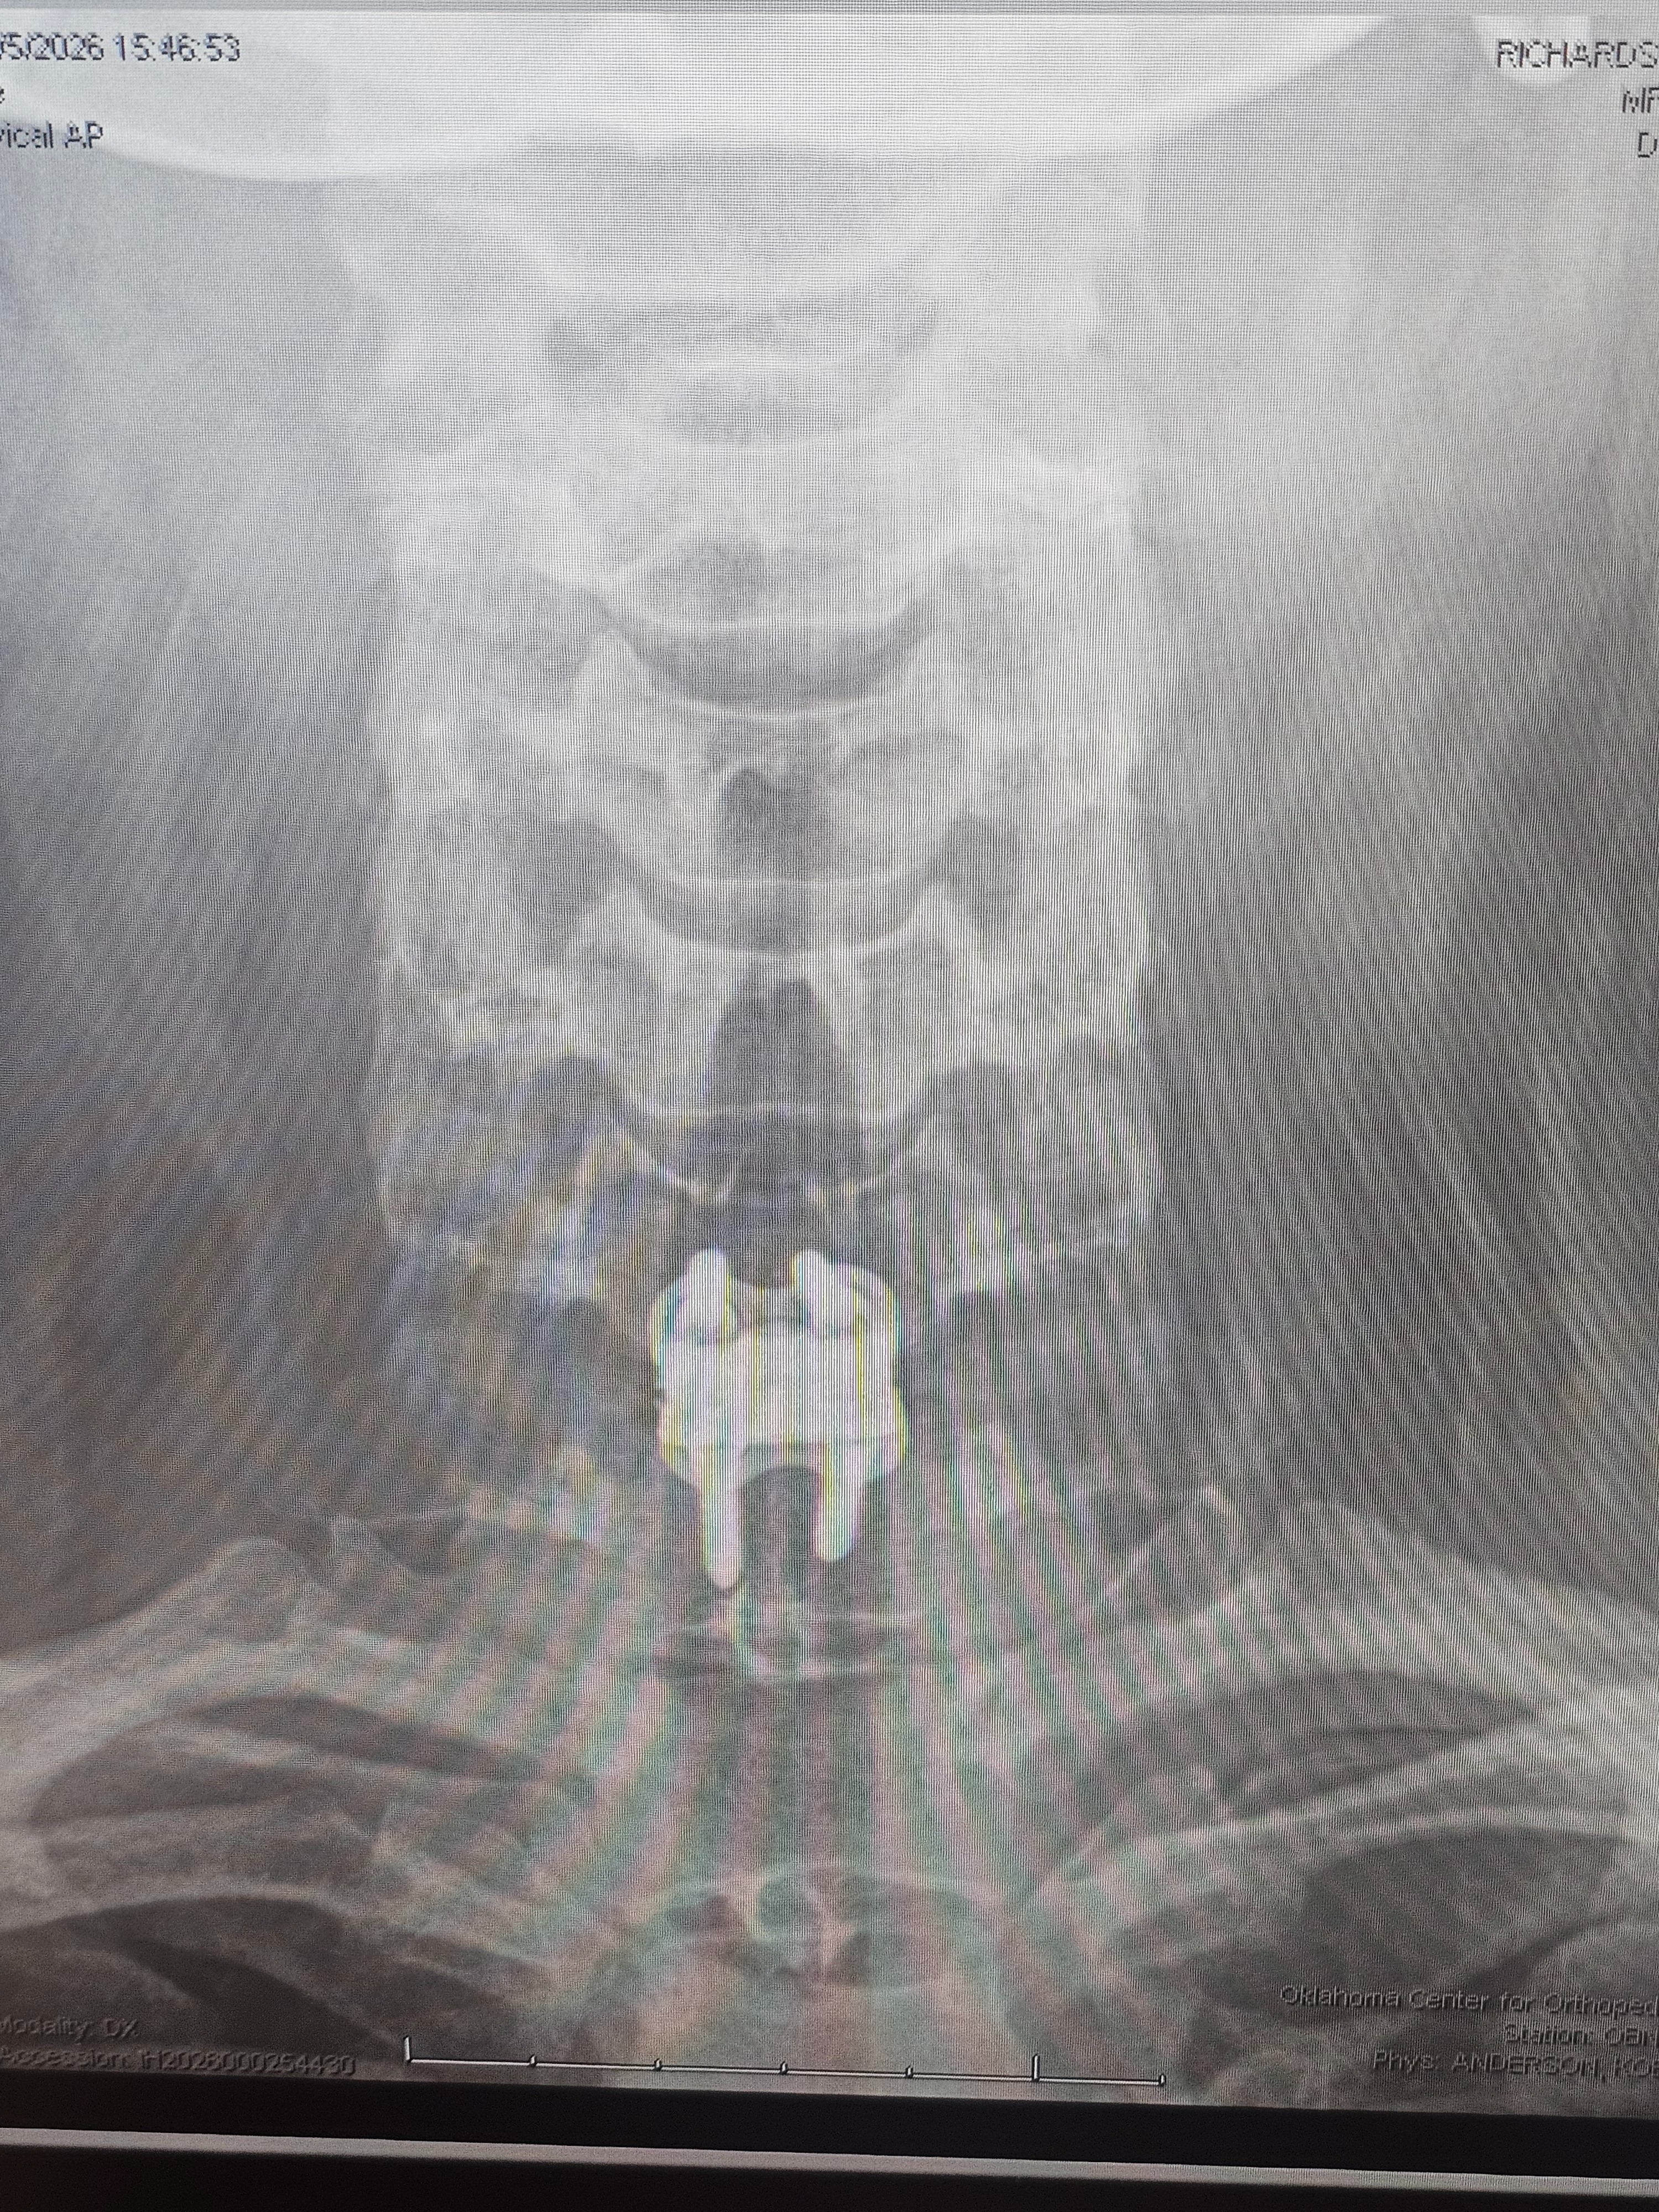

For those who may not know: In 2023 I was in a car accident that caused my disc between c6 and c7 yo herniate 5mm, pinching a nerve. I finally was able to get surgery to fix this in January of this year, but I've been out of work longer than expected and ran out of PTO. Unfortunately I don't exactly have parental support to cushion me in this time (RIP) my community has been saving me through this ❤️